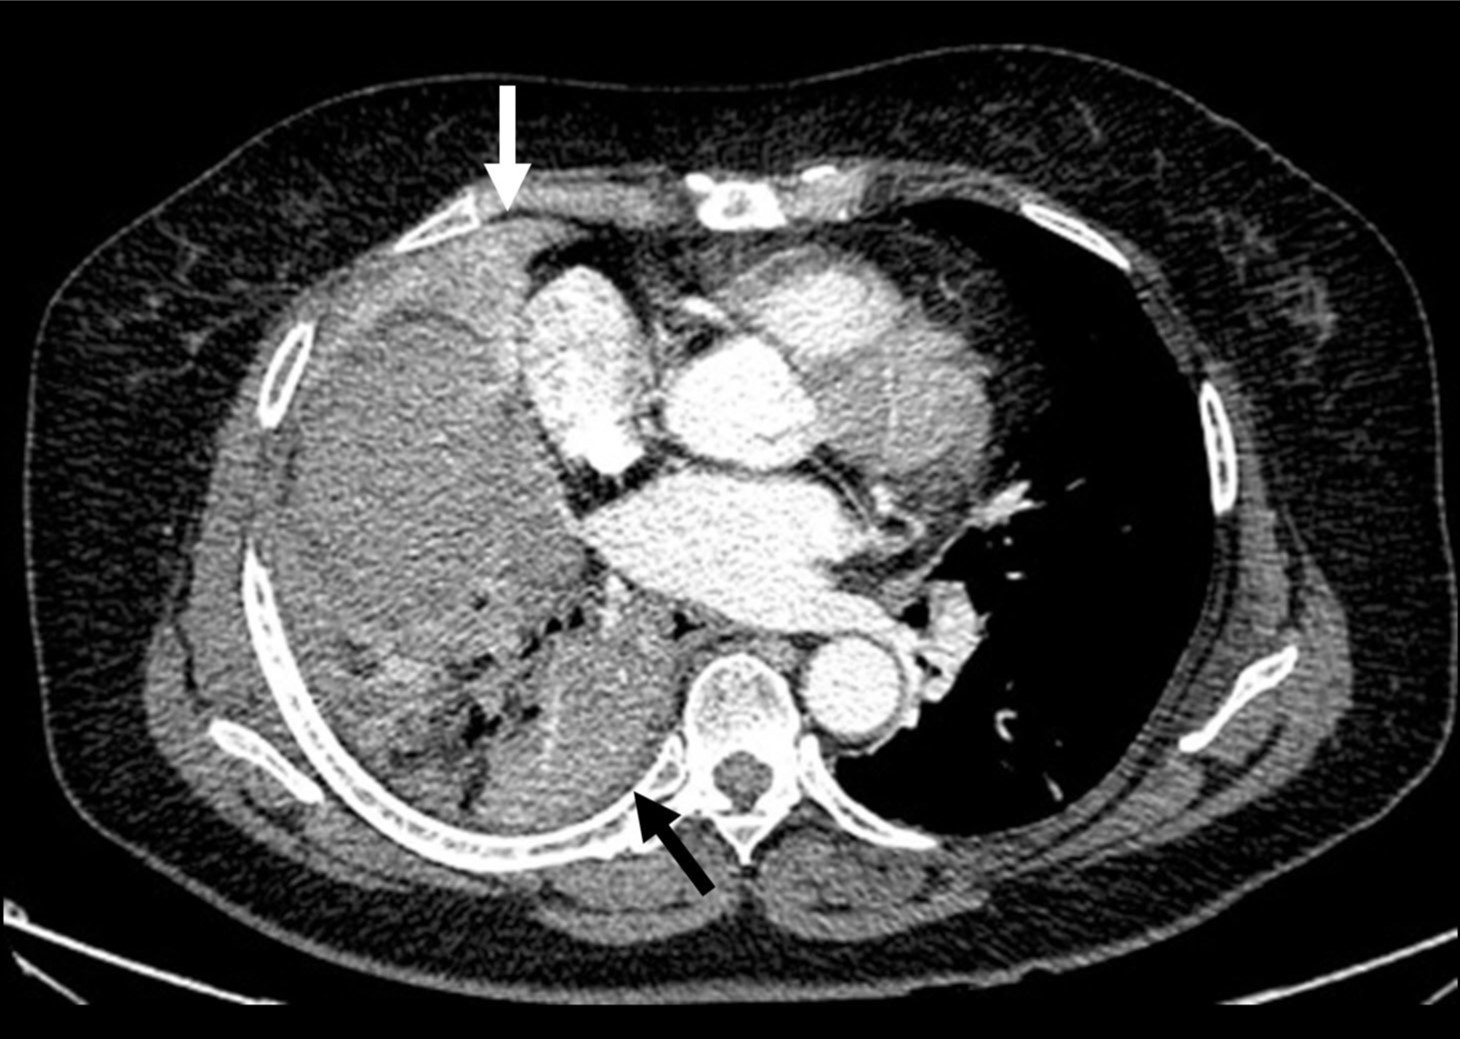

Fig. 1. B

Fig. 1B. A tortuous and dilated artery (arrow), suspected to be the right bronchial artery, appears to be originated from the right subclavian artery.